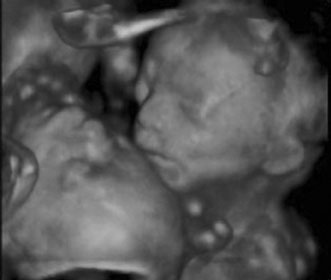

Maternal serum screening can identify pregnant women who are at an increased risk for having a baby with certain birth defects. Patient-specific risks for open spina bifida, Down syndrome and trisomy 18 (Edwards syndrome) (Fig. 1) can be determined by measuring the levels of certain proteins in maternal serum and combining those data with the patient's maternal age and clinical information.10 Women with a positive screen should be offered a definitive diagnostic test.

Fig. 1. Three-dimensional ultrasound showing typical pattern of trisomy 18. A clenched fist with the index finger overlapping the third and fourth fingers is distinctive of this disorder. Image courtesy of GE Medical Systems.